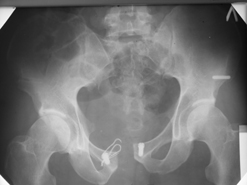

Диагноз : Сочетанная травма. ЗЧМТ. Перелом свода черепа. Ушиб головного мозга.Разрыв лонного и крестцово-подвздошного сочленений с нарушением целостности тазового кольца, с массивной забрюшинной гематомой и пропотеванием в брюшную полость. Перелом 10 ребра справа, осложненный гемопневмотораксом справа, правосторонней пневмонией на фоне ушиба правого легкого. Шок 3-4 ст. Больной поступил в отделение 07.03.2005г. в 16.00 в экстренном порядке через 30 минут после автодорожной травмы.Доставлен КСП. При поступлении состояние больного крайне тяжелое, явления травматического шока, А/Д-80/60 мм.рт. ст. ЧСС-120.В экстренном порядке поднят в операционную, интубирован, совместно с диагностическими мероприятиями лечение шока.При осмотре выявлены перелом 10 ребра справа, разрыв лонного и правого крестцово-подвздошного сочленений. Имеется линейный перелом теменной и височной костей слева с переходом на основание. Диагностическая лапароскопия 07.03.2005г. в 16.30-массивная забрюшинная гематома малого таза.Оставлена контрольная, дренажная трубка.Учитывая кровь в моче произведена цистография - данных за разрыв мочевого пузыря не найдено. Больной переведен в реанимационное отделение.За 08.03.2005г. из брюшной полости выделилось до 1500,0 мл, крови, часть крови реинфузирована. 08.03. в 06.30 наложен торокоцентез справа,удалено 100,0 мл. крови и 200,0 мл. воздуха .. Учитывая продолжающеееся кровотечение в брюшную полость из перелома костей таза, для исключения возможного разрыва внутренних органов 09.03.2005г. произведена Видеолапароскопия., на которой повреждения органов брюшной полости не выявлено.Одновременно произведен шов лонного сочленения проволокой и винтами, с одномоментным наложением стержневого аппарата на кости таза, с целью уменьшения кровотечения из разрывов тазовых сочленений, дренирование гематом. В последующем состояние больного оставалось тяжелым. 10.03.наложена нижняя трахеостома.Далее неоднократно производилась лечебно-диагностическая ФБС.С 10.03 выявлена правосторонняя плевропневмония. КТ головного мозга от 10.03-субарахноидальноекровоизлияние.Срединные структуры не смещены. КТ-контроль от 15.03-открытая моновентрикулярная гидроцефалия4 желудочка. Полисинусит. Постепенно состояние больного медленно прогрессировало к улучшению.С 24.03 переведен на самостоятельное дыхание, а 09.03 переведен в травматологическое отделение.Аппарат стержневой снят из-за перелома стержня (раскрутил больной самостоятельно).После госпитализации в наше отделение проведено дополнительное обследование Рентгекнография, КТ.Хотелось бы услышать Ваше мнение о дальнейшей тактике.-- С уважением, Leonid

Углядел билатеральное повреждение таза. Имеется вертикальная нестабильность со стороны перелома боковой массы крестца, ротационная с контрлатеральной стороны - чрезподвздошный разрыв кп сочленения. Разрыв лона, запирательные отверстия вроде целы.

DS. на сегодняшний день: Вертикальная двусторонняя нестабильная деформация таза, неправильно срастающийся перелом боковой массы крестца слева, срастающийся перелом крыла правой подвздошной кости, застарелый частичный разрыв правого кп сочленения, застарелый разрыв лонного сочленения.

План жизни - оперативное лечение. ЧКО таза (кольцевая опора), последовательная фиксация задних отделов с низведением перелома крестца, синтез лона пластинами, илиосакральное блокирование.

Нужно выполнить реостеосинтез симфиза пластиной (стабильный остеосинтез

пластиной винтов на 6). Странно, почему этого не сделали сразу, раз уж

вмешались открыто.